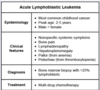

Pediatric Hematology and Oncology Flashcards

Acute leukemia is defined as a neoplastic proliferation of blasts > […]% on bone marrow biopsy.

Acute leukemia is defined as a neoplastic proliferation of blasts > 25% on bone marrow biopsy

e.g. ALL is diagnosed by presence of > 25% lymphoblasts in the bone marrow

Cytoplasmic aggregates of periodic acid Schiff (PAS) positive material are characteristic of […]-blasts.

Cytoplasmic aggregates of periodic acid Schiff (PAS) positive material are characteristic of lympho-blasts.

versus myeloblasts, which often have peroxidase positive granules and/or Auer rods

Cytoplasmic aggregates of peroxidase positive granules and/or Auer rods are characteristic of […]-blasts.

Cytoplasmic aggregates of peroxidase positive granules and/or Auer rods are characteristic of myelo-blasts.

versus lymphoblasts, which often have aggregates of periodic acid Schiff (PAS) positive material